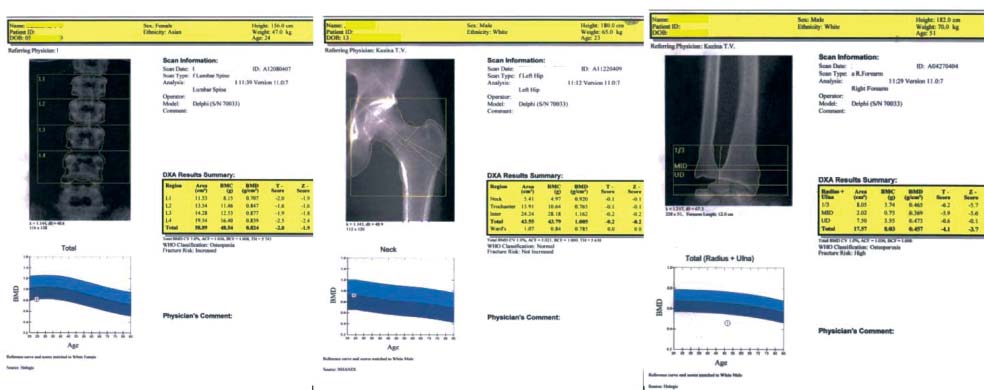

Проекционную МПКТ определяли с помощью двухэнергетической рентгеновской абсорбциометрии (Dual-Energy X-Ray Absorptiometry - DEXA) на рентгеновском денситометре фирмы «Hologic» (Соединенные Штаты Америки). Разрешающая способность выявления отклонений МПКТ от нормы составляла 1%. Лучевая нагрузка составляла 0,01 мЗв (10 мкЗв) за каждое стандартное исследование: 0,007 мЗв (7,0 мкЗв) при мгновенной оценке состояния позвоночника и 0,14 мЗв (140 мкЗв) при исследовании «все тело». МПКТ оценивали по трем

«зонам интереса»: поясничный отдел позвоночника в области LII–LIV, проксимальный отдел бедренной кости толчковой ноги и лучезапястный сустав доминирующей руки (рис. 1).

Рис. 1. Исследуемые зоны: а – поясничный отдел позвоночника в области L –L ; б – проксимальный отдел бедренной кости; в – лучезапястный сустав руки